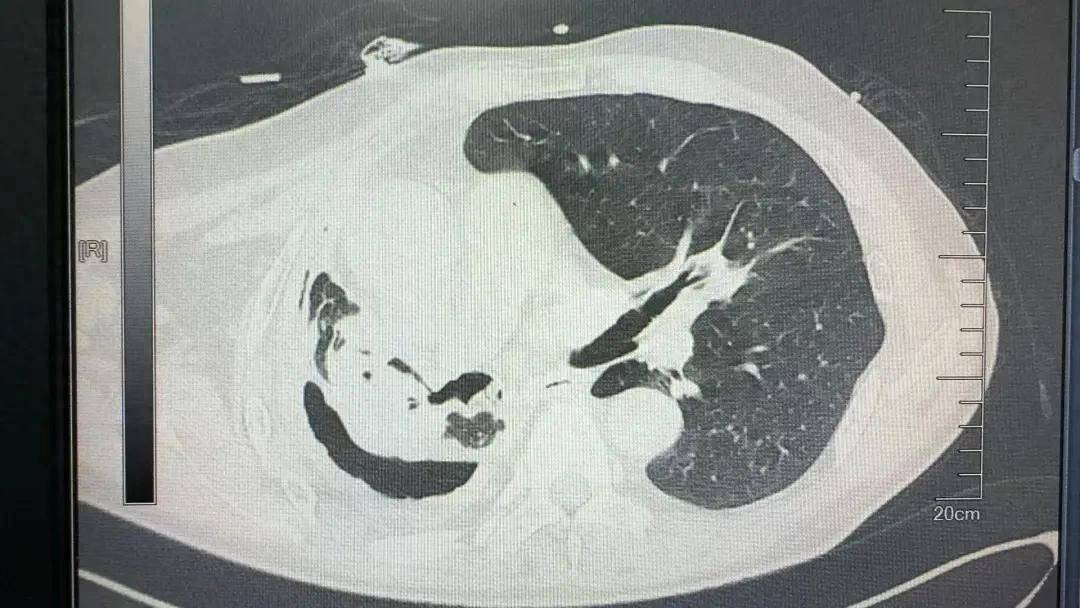

持续的咳嗽、7个月的胸闷。患者老段的右肺结核菌实变毁损,已丧失功能,形成的支气管胸膜瘘和不断产生的胸腔积液,致使他携带胸管1个多月了还无法拔除。

患者的冠状动脉重度狭窄,主动脉根部膨出一直径约5.7厘米的动脉瘤,主动脉瓣大量反流,一旦发生主动脉瘤破裂就会危及生命,这种情况同样需要手术治疗。

术中探查发现,患者胸腔封闭、广泛黏连、胸膜增厚,右肺因感染完全实变毁损,肺血管、支气管等解剖结构严重扭曲,手术难度大大增加。